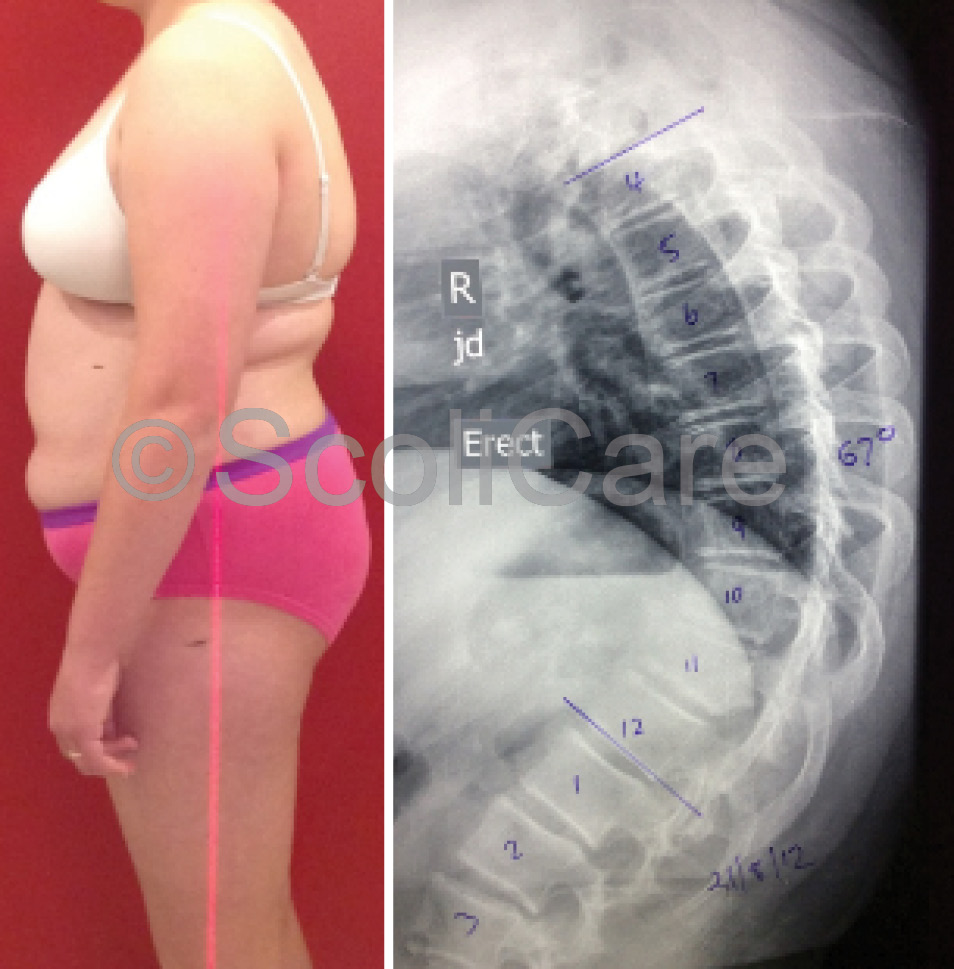

The patient was a pre-menarchal teenager who reported pain across the shoulder blades that extended from the upper thoracic spine down to the lower lumbar spine. The patient rated their pain as 6/10 on a visual analogue scale and stated that the pain and stiffness in their back was impacting on their daily activities. The patient was otherwise healthy. The physical examination revealed a significant increase in the patient’s thoracic kyphosis and lumbar lordosis (Figure 1), with marked angulation of the thoracolumbar spine during forward bending. There were no other significant clinical findings. A provisional diagnosis of Scheuermann’s kyphosis was made and confirmatory imaging was requested. Plain films taken soon after the examination highlighted an abnormal curvature in the sagittal plane – specifically a 67° hyper-kyphosis in the thoracic spine with an apex at T10. There was notable wedging of the T10 & T11 vertebrae in the lower thoracic spine.

Lateral x-ray indicating a hyper-kyphosis (Right)